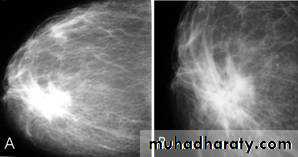

Mammography

The sensitivity of mammography for the detection of ILC reportedly ranges between 55-80% 8. Because of the limitations of mammography in detecting ILC, other modalities, such as sonography and MR imaging, are being used in evaluating clinically suspicious findings and known cancers to assess the extent of disease. ILC are more commonly seen on the craniocaudal (CC), compared to the mediolateral oblique (MLO).